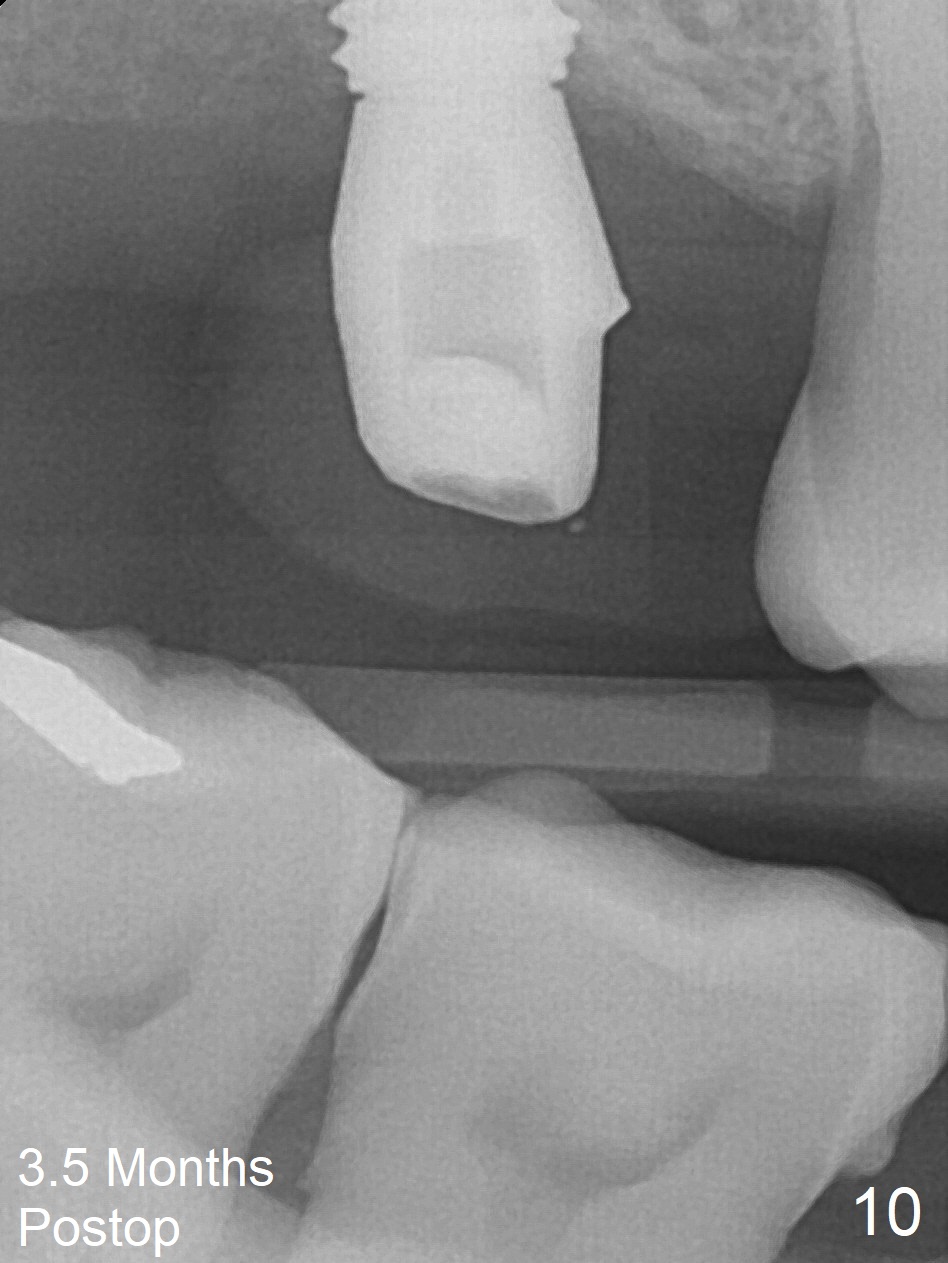

After extraction of the 3rd molar with mesial periodontal defect, osteotomy for 2nd molar implant is initiated in the mesial slope of the 3rd molar socket (Fig.1 red dashed line). When osteotomy is finished with IS drills and sinus lift with Magic Sinus Lifter (S-reamer with 11 mm stopper being short), a 4x10 mm dummy implant is placed with ~ 4 implant thread exposure (Fig.3). Following use of Lindamann bur to move osteotomy mesial and larger drill, a 4.5x10 mm implant is placed with 5-7 implant threads exposed distally (Fig.4,7 (~ 50 Ncm)). The bucco(B)-palatal(P) extent of the implant thread exposure is larger (Fig.5) than that associated with the 4 mm dummy implant (data not shown). The exposed implant surface is covered with Vera Graft (Fig.7*), Collagen plug and an immediate provisional after adjustment of abutment height (Fig.6,7). The bone density distal to the implant is low 3 months postop (Fig.8,9 CBCT) and 3.5 months postop (Fig.10,11). The permanent crown is cemented nearly 4 months postop. The distal cortical bone contacts the implant (Fig.12 ^), while the mesial bone increases in density (*) 2 years postop.